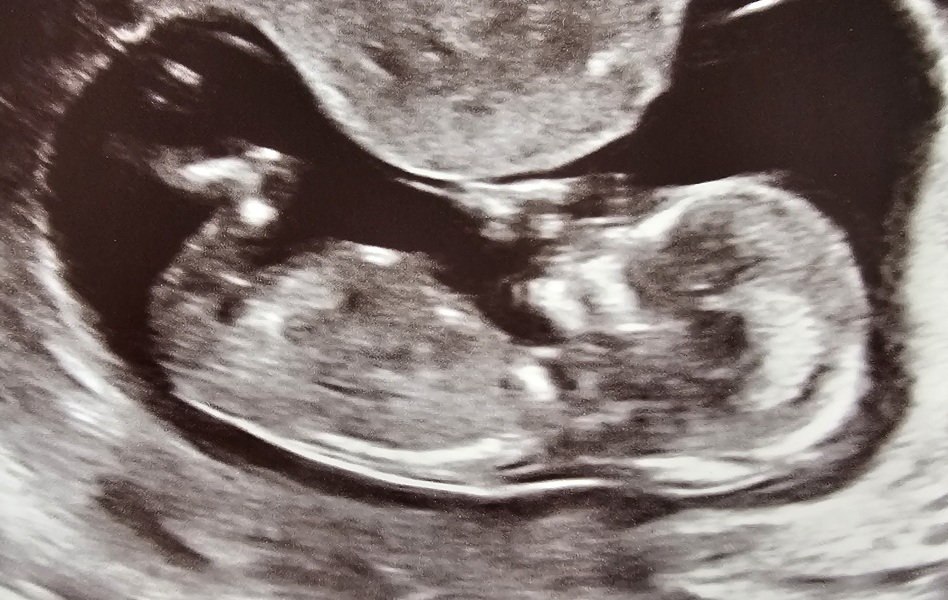

I had my 12 week scan on Tuesday and first thing she said was you are pregnant with twins. Shock Couldn't really take anything else in - and still slightly in shock! - but starting to adjust my visions/reality and grateful they are both ok and measuring at 60mm.

Anyone else expecting twins ?

LunaBear26 · 14/03/2026 13:29

@LibbyOTV I'm having twins! 13 weeks +1 today. Found out at an early scan at 9 weeks and just spent the last few weeks worrying about them! But all good at our scan yesterday.

I'm starting to get my head around it, but it is a bit crazy, isn't it?! We'll need a new car and our DS will probably need to move bedrooms too, as well as 2 nursery fees! How are you feeling about it? Do you know what type of twins they are yet?

I'm 13+6 so we must be very close together! Yeh it's a lot to get your head around, the practicalities as well as physical concerns.